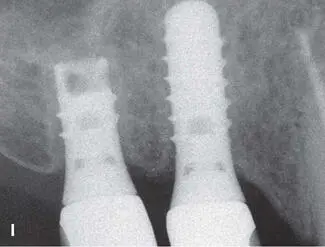

Early on, several complications were observed with both approaches, and modifications of the surgical techniques were proposed to improve the predictability of successful treatment outcomes. One frequent complication was the collapse of the ePTFE membranes, which reduced the volume of the regenerated tissue underneath the membrane. In addition, some of the regenerated sites demonstrated insufficient bone formation and the formation of a periosteum-like tissue underneath the membrane. 37 , 40 Therefore, bone fillers such as autografts or allografts were recommended by various groups, primarily to support the membrane and reduce the risk of membrane collapse. 54 – 56 The combination of ePTFE membranes and autogenous bone grafts provided good clinical outcomes for both approaches. Some of these patients are still being followed and documented up to 25 years after surgery (Figs 1-2 to 1-4).